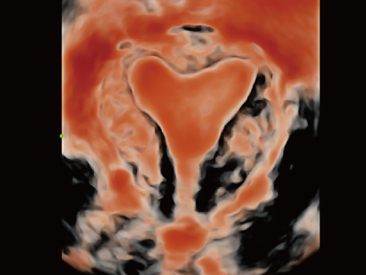

Seit der Gr├╝ndung des Unternehmens hat Mindray fortlaufend neue Wege zur Verbesserung der diagnostischen Zuverl?ssigkeit erforscht. Angetrieben von der revolution?rsten Technologie ZONE Sonography?, bringt die neue ZST+ Plattform von Resona 7 die Ultraschallbildqualit?t durch Zonenerfassung und Kanaldatenverarbeitung auf ein h?heres Niveau.

Neben der erstklassigen Bildqualit?t verbessert Resona 7 auch die klinischen Forschungsm?glichkeiten mit dem revolution?ren V Flow f├╝r die vaskul?re h?modynamische Bewertung und der intelligentesten Ebenenerfassung aus 3D-Datens?tzen f├╝r die f?tale ZNS-Diagnose. Mit der Kombination aus intuitiver, gestenbasierter Multi-Touch-Bedienung und allen wichtigen klinischen Funktionen ist das Resona 7 ein echter Wegbereiter f├╝r neue Ultraschall-Innovationen.

Die St?rken des Resona 7 sind bis ins kleinste Detail durchdacht. Seine erstklassige Bildqualit?t ist das Ergebnis einer erfolgreichen Fusion. Mindray und Zonare Medical Systems haben ihren Kernkompetenzen geb├╝ndelt, um ein Premiumsystem Wirklichkeit werden zu lassen. Dank der Vector Flow-Funktion k?nnen bei Gef??untersuchungen mehr als 400 Bilder pro Sekunde dargestellt werden. Somit entstehen ganz neue M?glichkeiten der Diagnose.